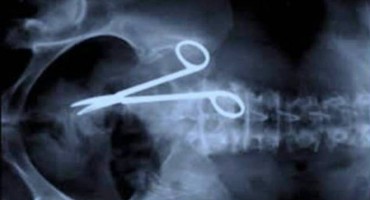

Epilog je to višegodišnjeg sudskog postupka koji je 41-godišnji Papac pokrenuo protiv mostarske bolnice u kojoj su mu liječnici na operaciji u utrobi zašili kirur&scaron…